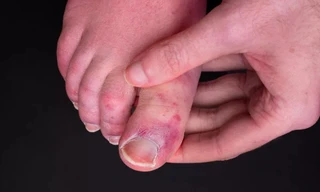

TPO - Một tình trạng bí ẩn được gọi là "ngón chân COVID" cuối cùng có thể có lời giải thích sau khi các nhà nghiên cứu tìm hiểu những người nhiễm COVID-19, rồi bị phát ban ở ngón chân.